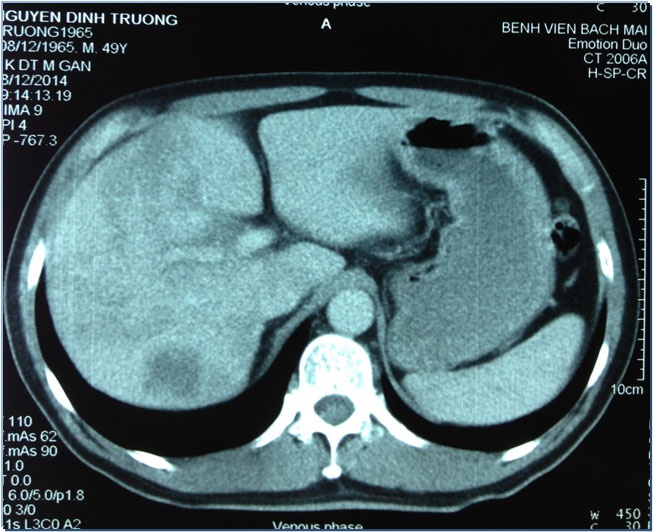

Đây là một bệnh nhân nam (59 tuổi, Hà Nội) vào viện vì đau tức hạ sườn phải. 2 tháng trước khi vào viện, bệnh nhân có đau tức hạ sườn phải, người mệt mỏi, ăn kém, sụt 2kg/tháng. Sau khi phát hiện u gan tại một phòng khám tư, bệnh nhân đã vào BV Bạch Mai để khám. Tại đây bệnh nhân được phát hiện khối u rất to ở gan phải, với kích thước 8,5x7,2cm. Gan trái cũng được phát hiện khối u kích thước 3,1 x2,1cm.

Tuy nhiên chỉ số chỉ điểm ung thư lại cho thấy bệnh nhân bị di căn từ một loại ung thư khác trong cơ thể. Nghĩ đến nguy cơ ung thư trực tràng, các bác sĩ đã nội soi và lấy mẫu sinh thiết phát hiện bệnh nhân bị ung thư đại tràng xích ma loại biểu mô tuyến di căn gan.

“Với khối u lớn như vậy sẽ không thể phẫu thuật. Vì thế, chúng tôi đã quyết định sử dụng phương pháp hạt vi cầu phóng xạ để giảm kích thước khối u cho người bệnh. Kết quả sau điều trị kích thước khối u giảm xuống còn 3,0x3,5cm. Lúc này bác sĩ mới có thể can thiệp phẫu thuật cắt bỏ đoạn TT lấy u gan di căn”, TS Thái cho biết.